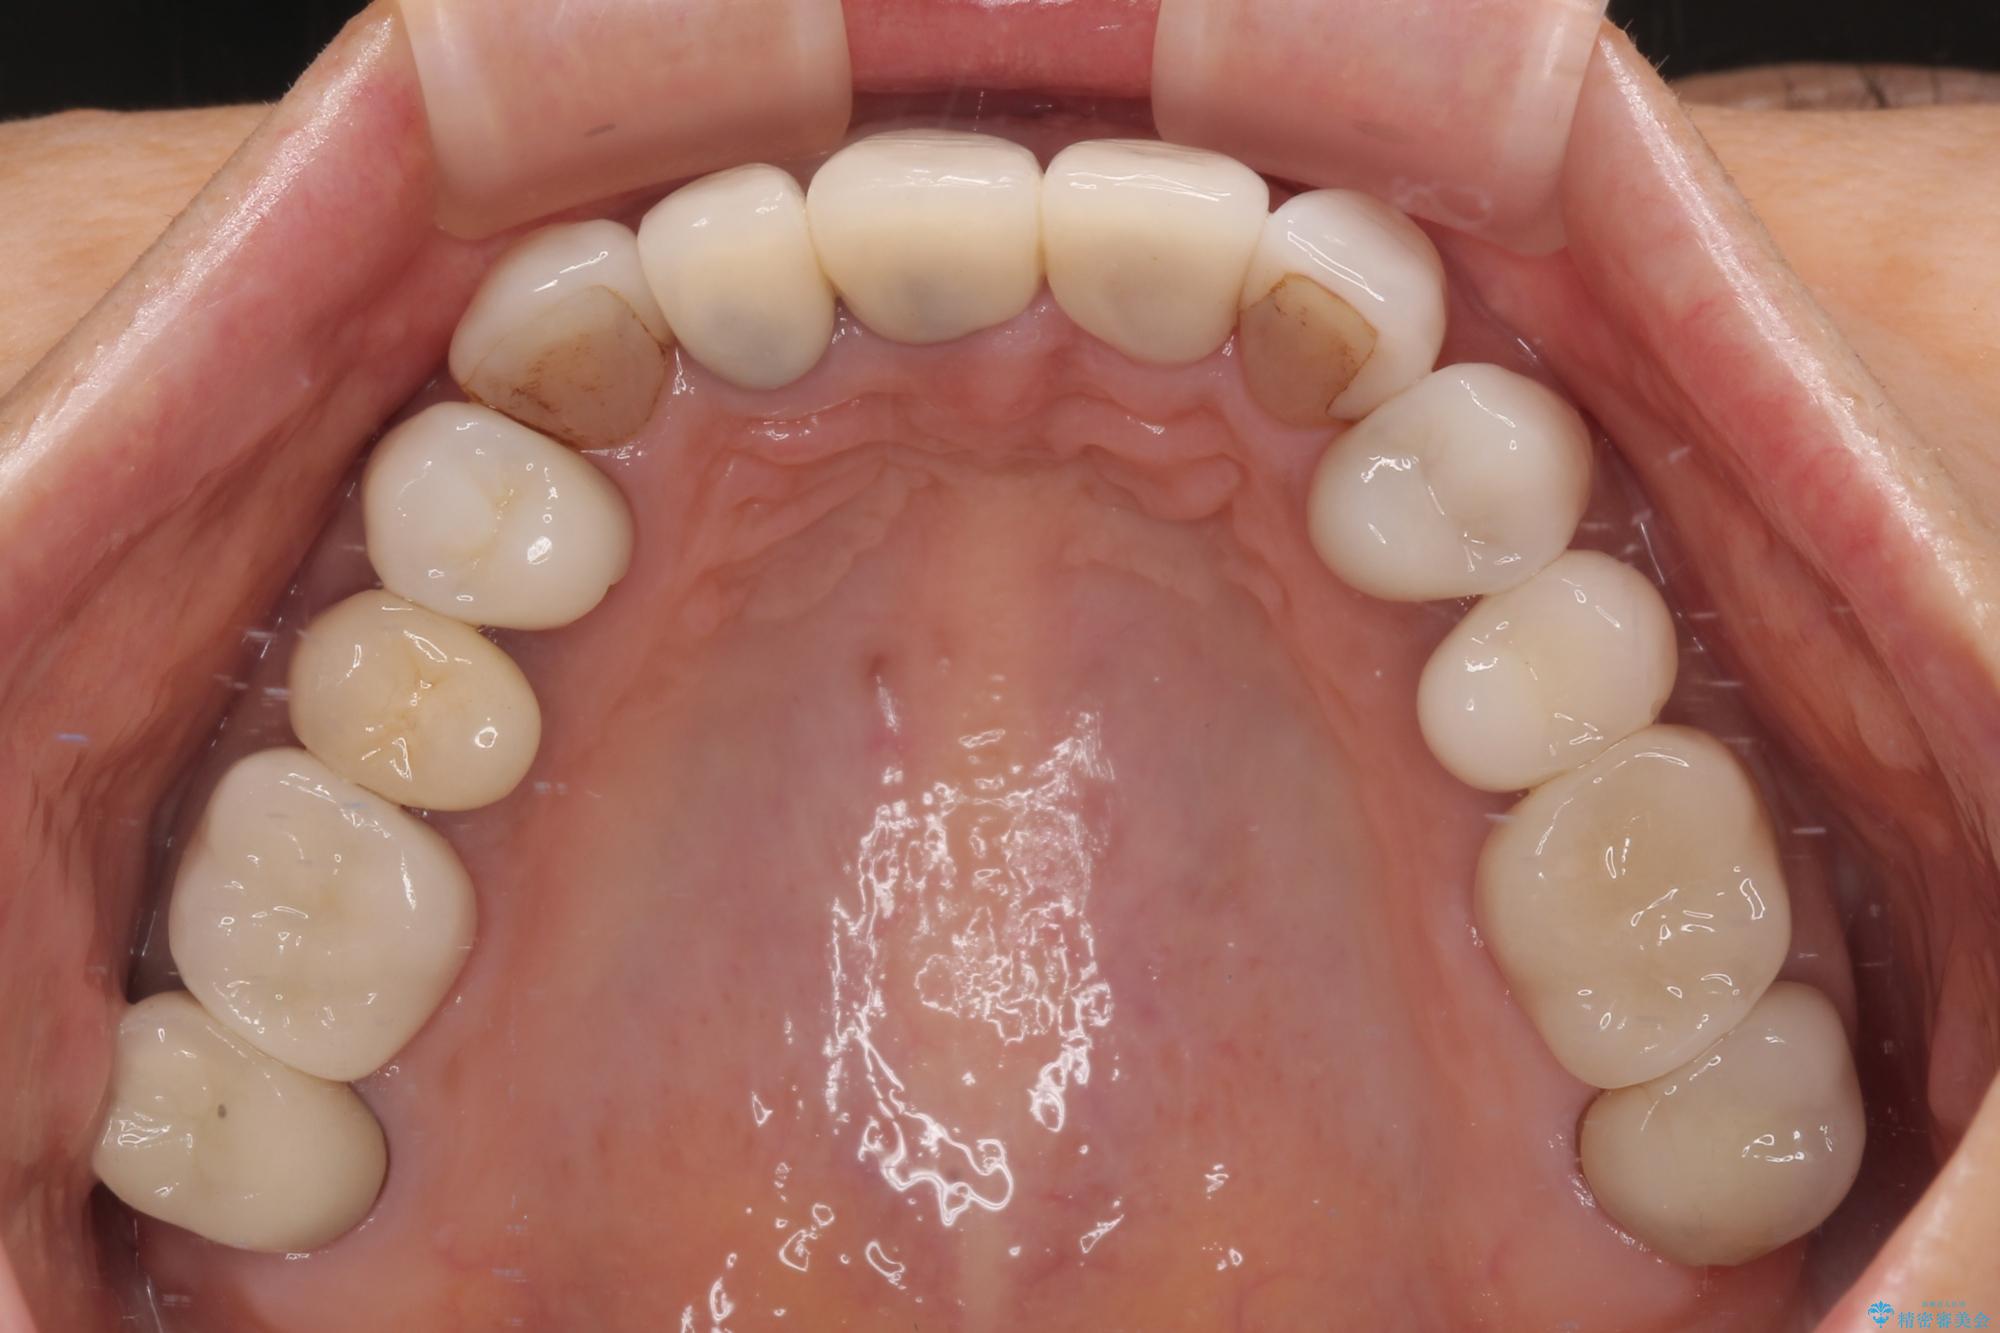

- 前歯のセラミックが欠けたり色調が不揃いであったりすることを気にして来院された患者様です。

20年以上前から、むし歯になったり詰め物が欠けたりする度に部分的に処置を行ってきたそうですが、この際統一感のある前歯にしたいとのことで、上顎前歯9本をオールセラミッククラウンによる補綴治療を行うこととしました。